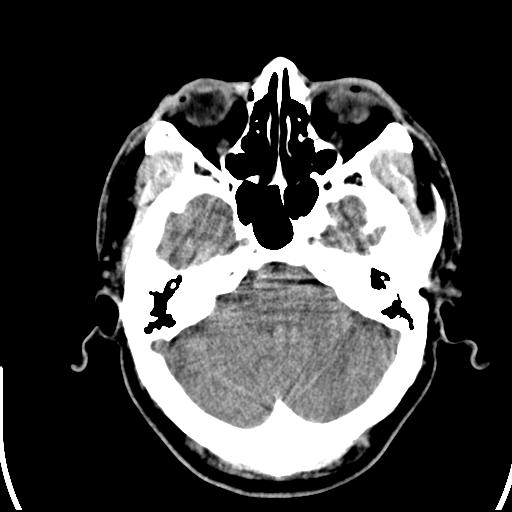

标题: CT25435:头皮下高密度影???

头皮下高密度结节影???临床上在老年男性比较常见。大家看看是什么?成因是? 本例患者,男性,51岁。外伤来诊。无染发史及发根植入史。